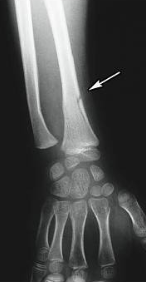

colles fracture